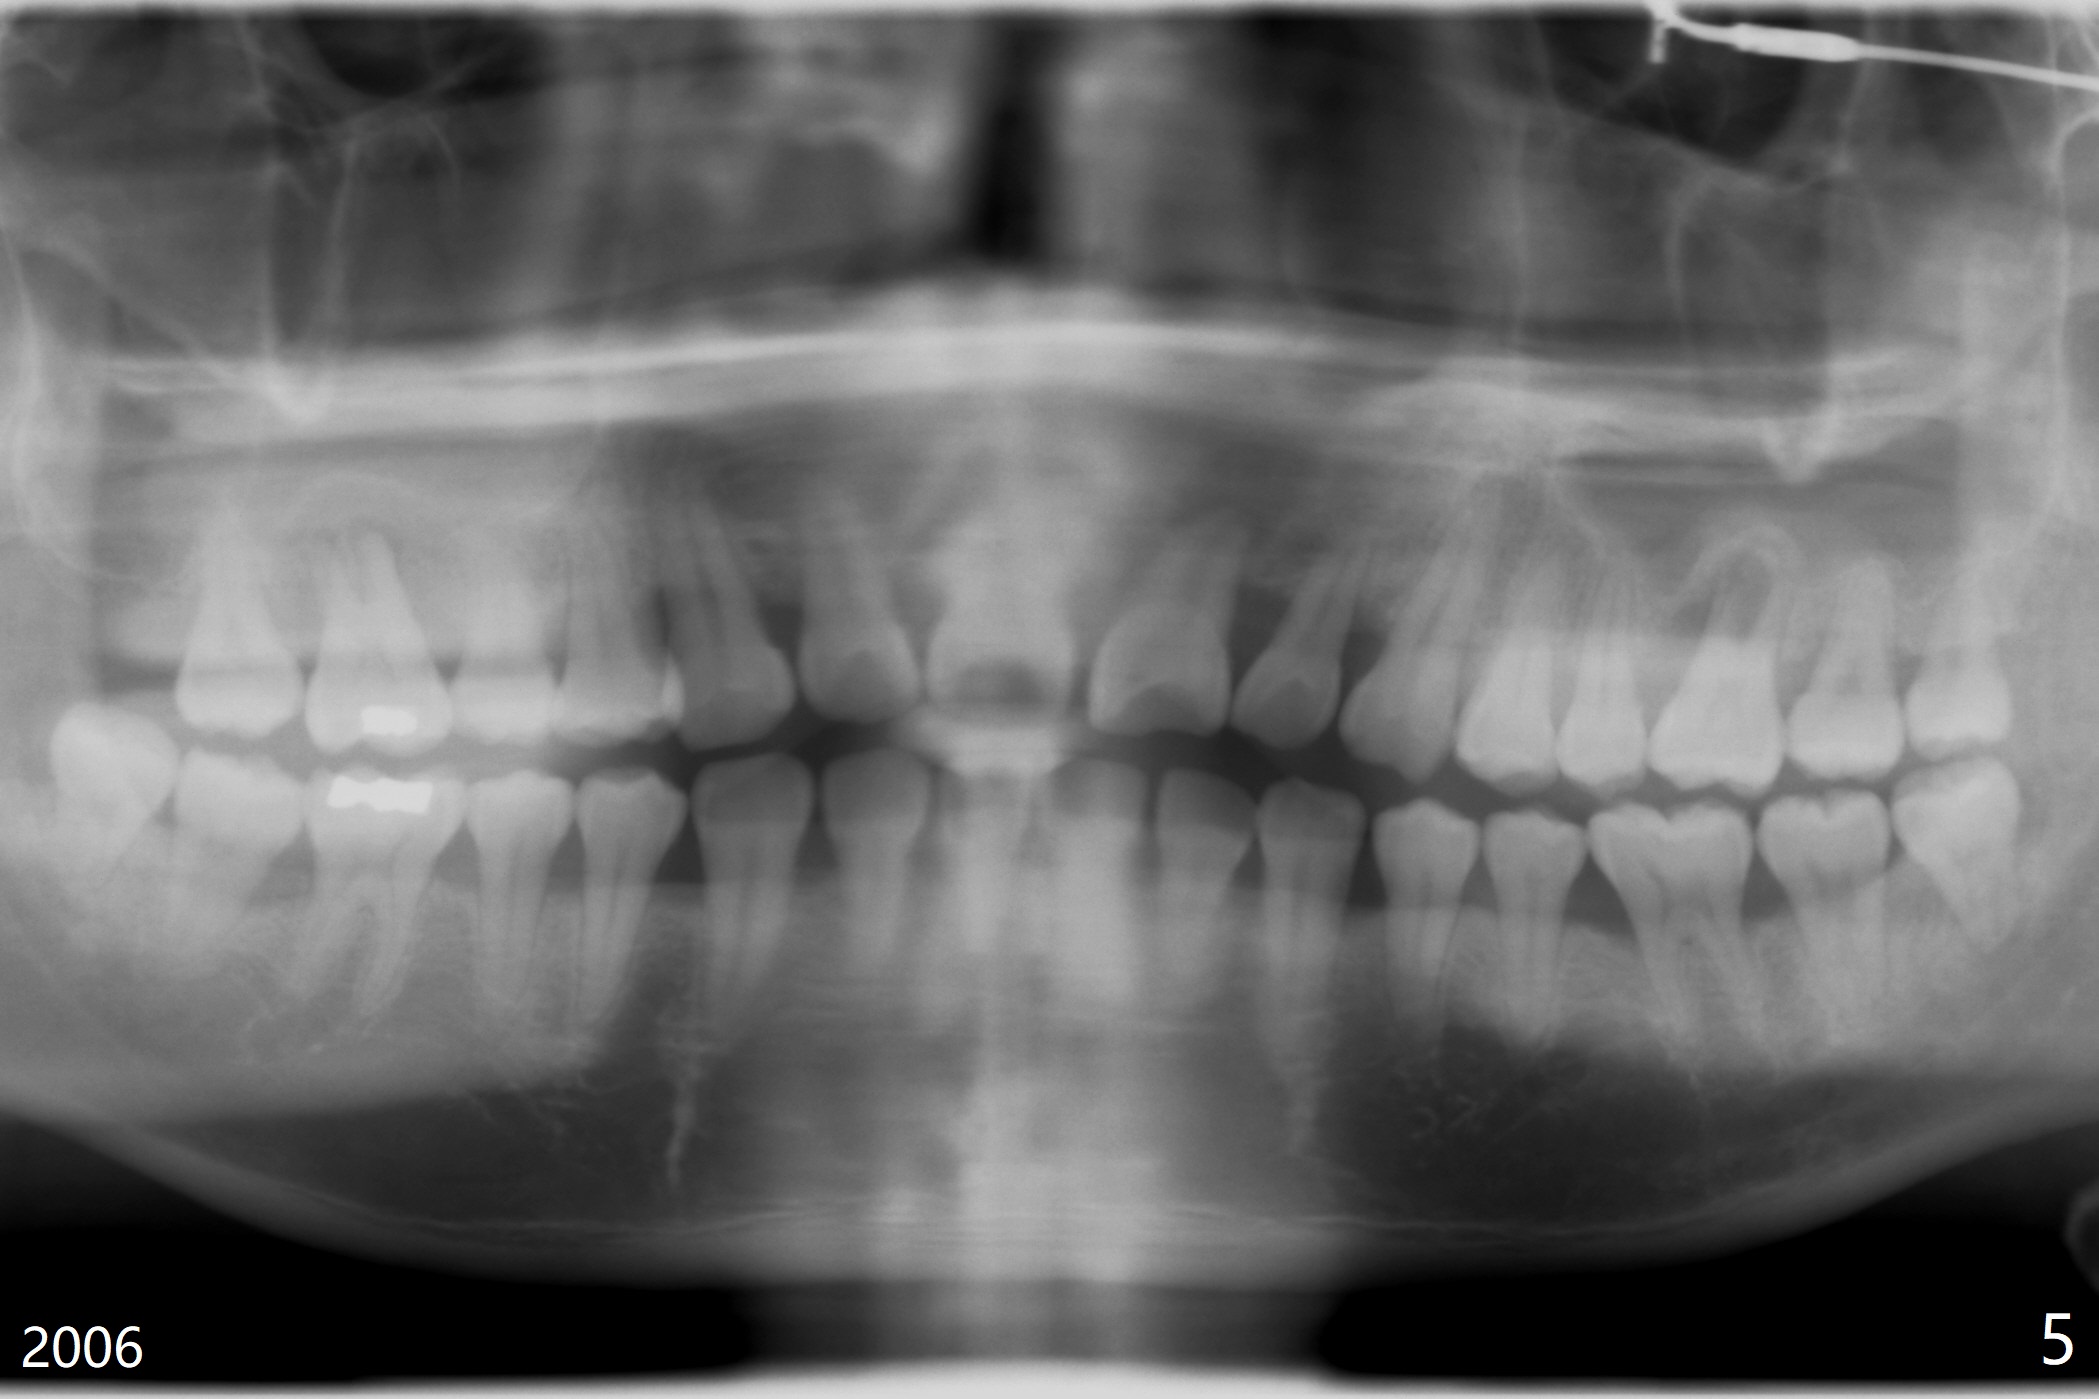

A 41-year-old man has had severe periodontitis at #14 for the last 11 years (Fig.5).